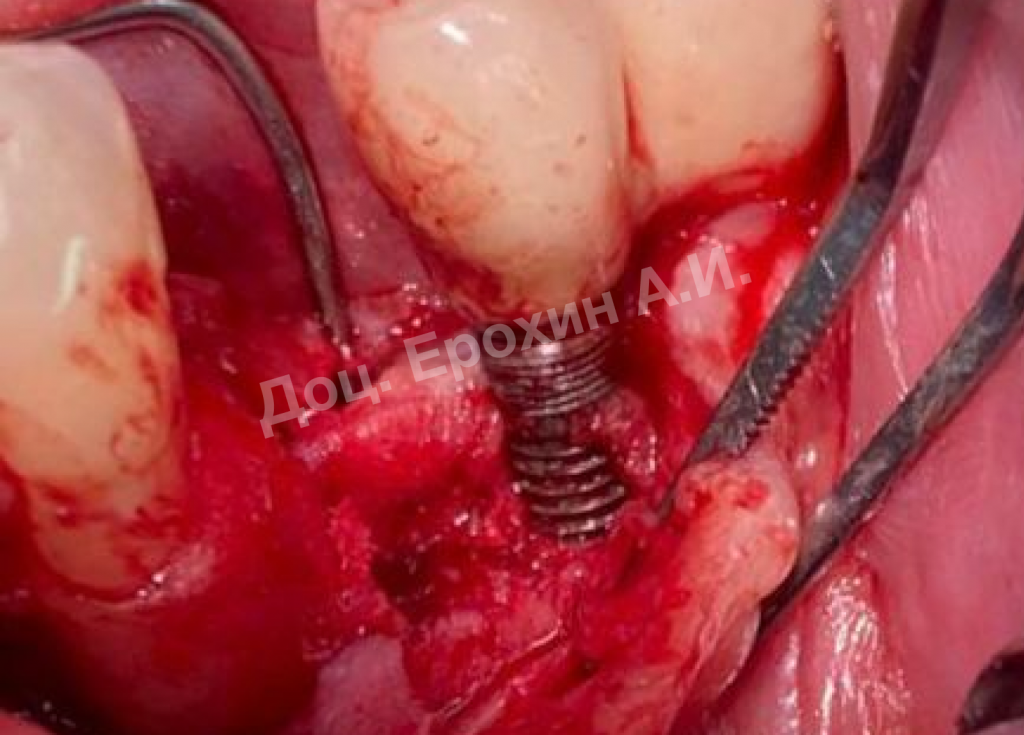

Тентовые винты имеют широкие шляпки, которые позволяют мембране опираться на них, тем самым препятствуя изменению профиля регенерируемого участка.

Кейс доцента Ерохина Алексея Ивановича